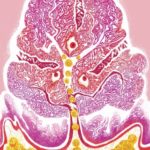

Un team internazionale guidato dal Professor Dilson Rassier del Dipartimento di Kinesiologia e Educazione Fisica alla McGill, ha scoperto, lavorando con conigli transgenici con la mutazione R403Q, che in questi conigli, singole molecole di miosina e miofibrille (i bastoncini di base simili a bastoncelli nei muscoli) producono meno forza e una velocità massima di contrazione inferiore rispetto alle molecole isolate da cuori sani.

I ricercatori hanno raggiunto questa conclusione utilizzando tecniche avanzate come la microscopia a forza atomica e i test di motilità molecolare (che consente di visualizzare i movimenti di queste proteine ​​in vitro) per osservare più da vicino ciò che stava accadendo all’interno delle molecole di miosina e anche all’interno delle miofibrille.